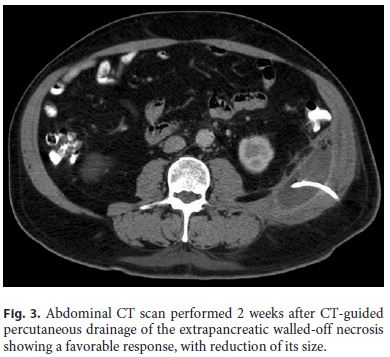

Even though there was a favorable response in the beginning, 10 days later, there was a new fever peak, of 38.6 ° C, and IP rose again (with a maximum CRP of 7 mg/dL). Abdominal CT showed increase in the left abdominal wall collection size (13 × 7 × 8 cm), corresponding to an extrapancreatic WON (Fig. 2).

The patient was submitted to CT-guided percutaneous drainage of the collection with placement of an 8.5-Fr pig-tail catheter. Citrobacter freundii was isolated in the purulent fluid, susceptible to piperacillin/tazobactam, which was administered for 14 days. Three-times a day irrigation and washing of the WON with a 0.9% saline solution was performed. The patient reported symptomatic improvement, IP normalized, and the collection regressed (Fig. 3), so the drain was removed 15 days after its insertion and the patient was discharged.